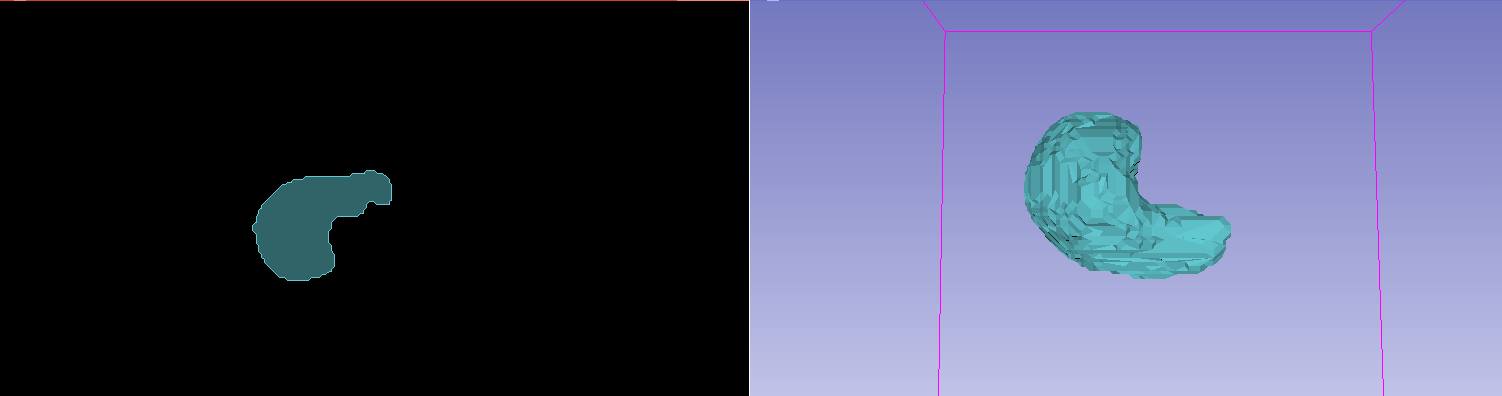

![[06] Read DICOM RT plan file, get RT plan parameters - YouTube](https://i.ytimg.com/vi/zl0PR4oHDKg/maxresdefault.jpg)